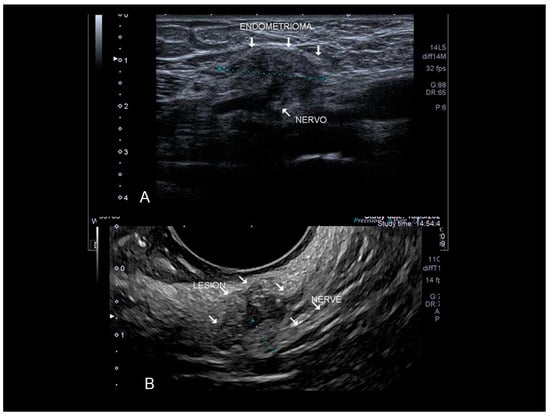

3.7. Other (Nonabdominal and Nonthoracic) Sites: Vascular, Lymphatic, and Central and Peripheal Nervous Systems

Only peripheral nerves can be investigated using ultrasound [33]. The most investigated nerve, due to the typical symptomatology, is the sciatic nerve. Ultrasonography, extending from the sciatic notch to the level of the ischial tuberosity, shows that the sciatic nerve was “engulfed” in a large, perineural, hypoechogenic, inhomogeneous lesion with an irregular contour corresponding to an endometrioma. Other nerves can be involved. We observed retroperitoneal implant in the topography of Latzko space (also called lateral pararectal space) with nerve involvement (Figure 22).

Figure 22. Endometriosis of very lateral retroperitoneal implant (see white arrow) in the topography of Latzko space with nerve involvement confirmed at surgery. The clearest portion measured probably refers to the compromised epineurium. Findings confirmed by MRI and electroneuromyography (A). The last picture is a nerve branch involvement by wall endometrioma in the topography of external iliac vessels (see white arrow) (B). Confirmed by surgery.